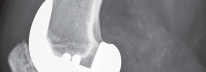

الفحوصات التصويرية الأشعة السينية والرنين المغناطيسي

*

الأشعة السينية (X-rays):

هي الفحص الأول والأكثر شيوعًا. تظهر الأشعة السينية بوضوح مدى تآكل الغضروف عن طريق إظهار تضيق المسافة بين العظام، بالإضافة إلى وجود نتوءات عظمية (Osteophytes) أو تشوهات في المفصل.